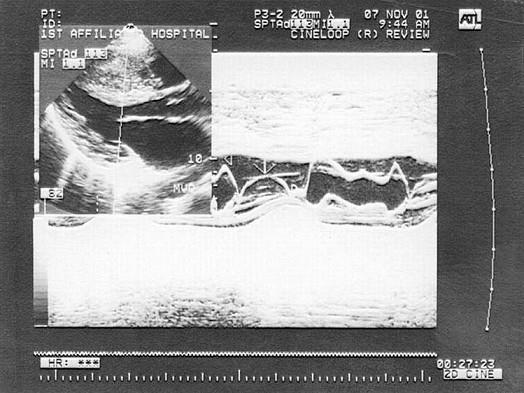

该病例最有可能诊断是?(?)A.高血压病B.主动脉瓣下狭窄C.肥厚型梗阻性心肌病  D.非梗阻性心肌病E.主动脉瓣狭窄

问题 该病例最有可能诊断是?(?)

选项 A.高血压病 B.主动脉瓣下狭窄 C.肥厚型梗阻性心肌病   D.非梗阻性心肌病 E.主动脉瓣狭窄

答案 C